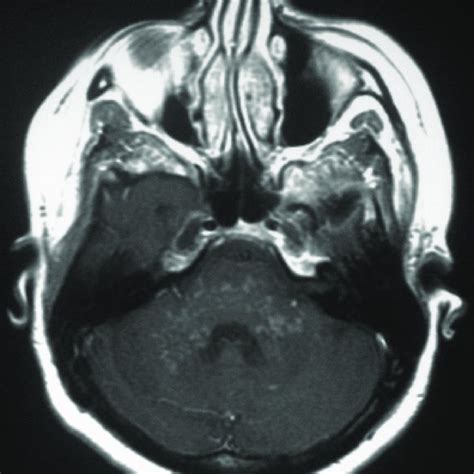

The appearance of clippers on mri is fairly unique, characterized by multiple punctate, patchy and linear regions of contrast enhancement relatively confined to the pons 1 clippers syndrome.

The appearance of clippers on mri is fairly unique, characterized by multiple punctate, patchy and linear regions of contrast enhancement relatively confined to the pons 1 clippers syndrome clippers. In addition, we also present a unique case of newly described autoimmune entity clippers syndrome.